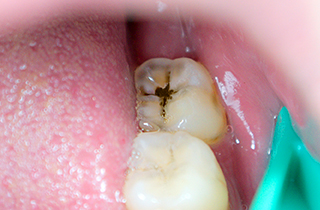

Caries treatment for decay visible during clinical examination

-

Enamel Caries

Decay limited to the enamel, the outer layer of the tooth, with little or no pain.

Resin Restoration

Dentin Caries

Decay has progressed into the dentin beneath the enamel, and sensitivity may occur when eating hot or cold foods.

Inlay